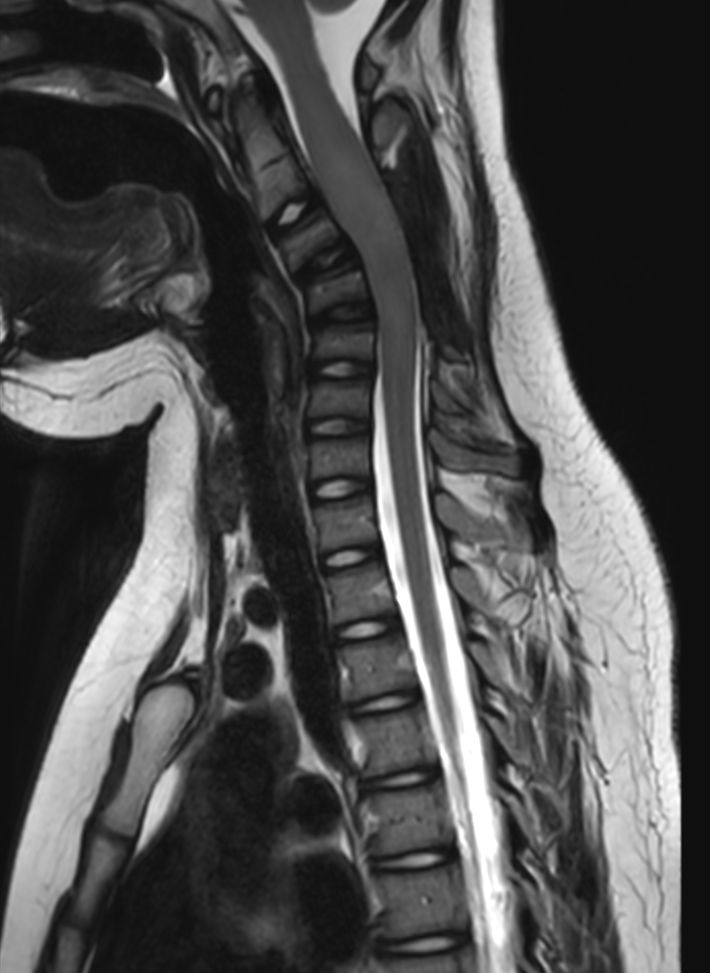

Total Spine on a 14 year old patient

Pediatric 14 year old patient with a lesion in the cervical spine

Sagittal T2w TSE (T-Spine)